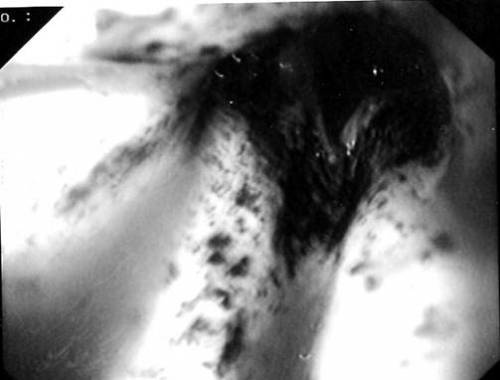

- צילומי ושט וקיבה, ב-CT חזה ובטן המתבצעים בשלבים המאוחרים יותר של הטיפול, ידגימו הרס הרירית, כיבים, היצרות הוושט או חסימת הנהור, או דלפים מהוושט. הפרעות במעבר, ושט בצורת ספירלה, בצקת הרירית וכיבים אורכיים מעידים על כווייה בוושט. בכוויות חמורות ניתן לראות אטוניה והתרחבות או נוקשות והיצרויות של הוושט. בקיבה נראה נזק לרירית הקיבה, כיבים או התנקבויות. הכוויות השטחיות מתרפאות במלואן, ואילו העמוקות מותירות צלקת, לכן יש להמשיך לעקוב אחרי חולים אלה תקופה ארוכה. בשלב הכרוני משמשים צילומי הוושט והקיבה כלי עזר חשוב במעקב אחר התקדמות התהליך הפיברוטי בוושט ובקיבה.